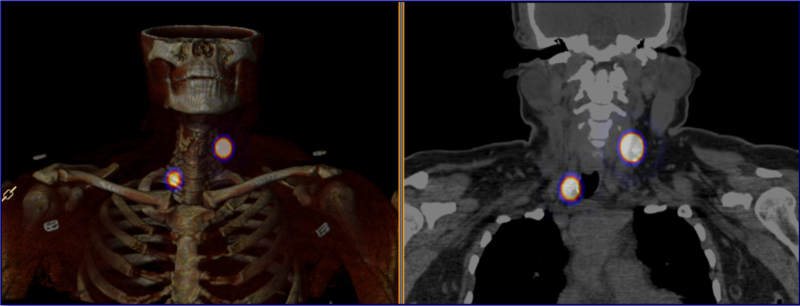

Las figs 2-5 ilustran casos de la serie analizada.

Se analizaron 17 casos, 15 mujeres y 2 hombres, con edad promedio de 50,4 años (23-73 años). Se identificó carcinoma papilar clásico en 15 pacientes y papilar variante folicular en 2, con varias intervenciones previas por LLRCT (en promedio 2,3 intervenciones por paciente). La TGB pre quirúrgica promedio de 23,9 ng/ml (3-123 ng/ml), descendió posterior a la cirugía a un valor promedio de 4,6 ng/ml (aunque fue medida sólo en 12 casos). En la tabla 2 se resumen los resultados.

En cuanto a la efectividad quirúrgica, se extirpó el 100% de las lesiones radiomarcadas (17/17); de ellas, 16/17 (94,1%) fueron positivas para LLRCT. En el 47% (n=8) fueron recurrencias y en 53% (n=9) adenopatías secundarias.

El tiempo operatorio promedio fue de 57,3 min (30-100 min). Los tiempos más prolongados correspondieron a un caso que requirió vaciamiento ganglionar lateral adicional y a otro con extensa fibrosis que debió ser reintervenido por hematoma post quirúrgico, única morbilidad grado 2 encontrada. El tiempo de hospitalización osciló entre 16 y 48 horas, con un promedio de 19,69 horas (corresponde aproximadamente al 50% del promedio histórico de la institución de 40,5 horas). De acuerdo a la opinión subjetiva de los cirujanos actuantes, la complejidad quirúrgica y la morbilidad fueron menores que con el procedimiento convencional.

Efectos del AMESPECT

- En 13/17 casos (76%), incrementó un 25% el tamaño detectado de las LLRCT respecto a la ecografía inicial (de 12,6 mm promedio a 16,8 mm.).

- Se reconocieron 22 nuevas lesiones (129% más) sospechosas de LLRCT en 11/17 pacientes (65%), en quienes modificó el plan quirúrgico; 82% de las nuevas lesiones fueron positivas para carcinoma tiroideo.